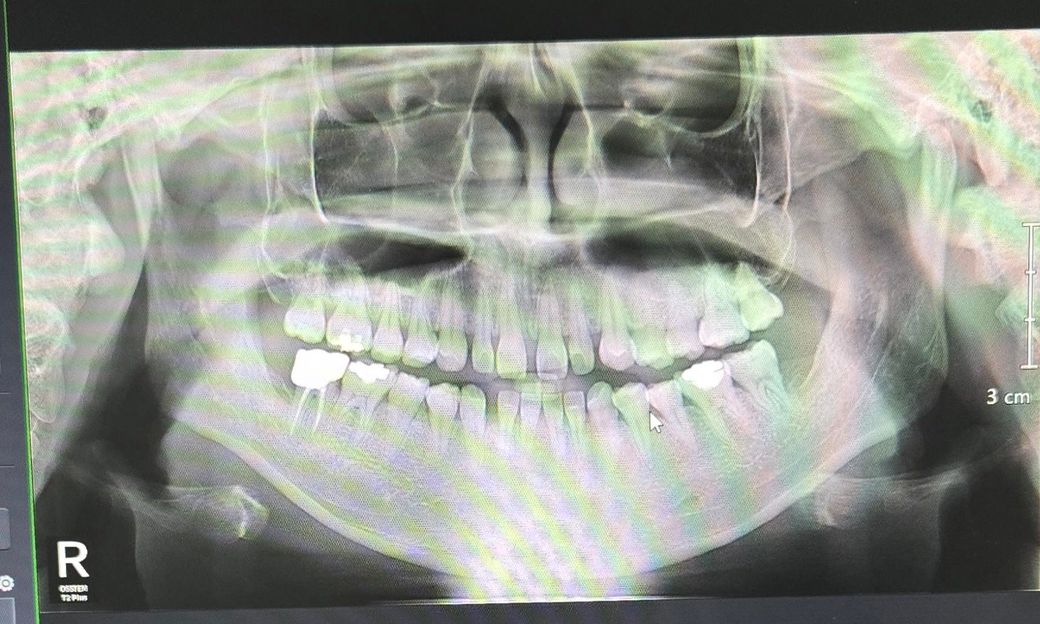

사랑니는 무조건 발치를 안해도 되나요?

왼쪽 위 끝에 어금니가 시리고 통증이 있어서 치과

를 다녀왔습니다.

저는 끝에 어금니가 평범한 치아인줄 알았는데 진료

를 해보니 끝에 어금니가 사랑니이고 원래 치아는

선천적으로 나지 않은것 같다고 하셨습니다.

발치를 해야되냐고 물어보니 그냥 써도 된다고 하셨

는데 나중에 문제 생길까봐 너무 걱정이 됩니다.

사진도 올리는데 이정도면 그냥 써도 문제없이 무방

할까요?

• 1번 째 사진

사진상으로는 사랑니가 잇어 보이진 않습니다. 사랑니 발치를 하지 않으셔도 될것같습니다.

왼쪽 위 끝 치아가 7번 missing이고, 원래는 사랑니라는 점은 사진으로 봐선 저는 잘 모르겠습니다

그 치아 정체가 뭐든 7번에 준해서 아프면 뺄게 아니고 치료를 받아야죠